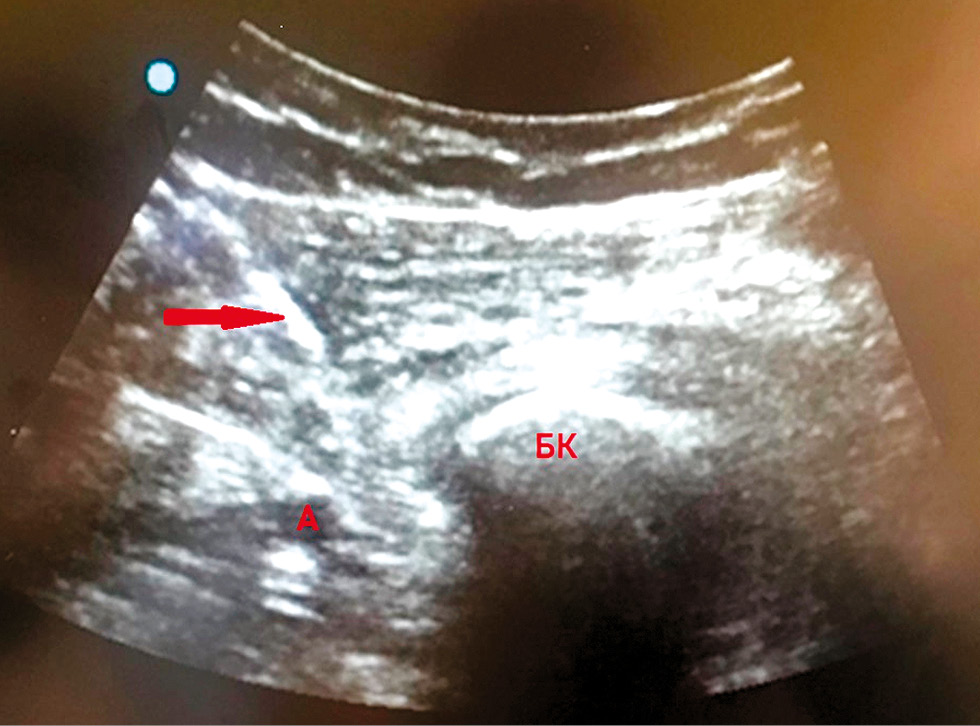

В 1-й группе (n=34) пациентам были выполнены блокада iPACK и блокада приводящего канала. Блокада приводящего канала выполнялась на уровне средней трети бедра. Ультразвуковой датчик помещали поперёк медиальной части бедра, в средней точке между паховой складкой и медиальным мыщелком бедра, чтобы визуализировать бедренную артерию, которая расположена под портняжной мышцей, и кожную ветку бедренного нерва. Под ультразвуковым контролем кончик иглы помещался впереди по отношению к артерии и немного глубже задней фасции портняжной мышцы, после чего вводился местный анестетик. IPACK-блок выполняли по модифицированной методике, разработанной в нашей клинике. При этом раствор местного анестетика вводился между бедренной костью и подколенной артерией под ультразвуковым контролем, где располагаются суставные ветви большеберцового нерва, общего малоберцового и запирательного нервов, обеспечивающие сенсорную иннервацию задней капсулы коленного сустава (рис. 1). Модифицированная методика отличалась тем, что игла располагалась в медиально-каудальном направлении и была ориентирована относительно подколенной артерии спереди и сбоку (рис. 2). Преимуществом методики является снижение риска травматизации подколенной артерии и вены тупоконечной иглой, а также простота доступа к конечным сенсорным ветвям, иннервирующим заднюю капсулу коленного сустава.

Рис. 2. Ультразвуковое изображение выполнения iPACK-блока (направление иглы сверху вниз под углом 45° по направлению к мыщелку бедренной кости (БК), к пространству, располагающемуся между мыщелками БК и подколенной артерией (А), инфильтрация производится по ходу движения иглы, с основным введением раствора между подколенной артерией и мыщелками бедренной кости)

Fig. 2. Ultrasound image of the iPACK block execution (direction of the needle from top to bottom at an angle of 45 ° towards the condyle of the femur (BC), to the space located between the condyles of the BC and the popliteal artery (A), infiltration is performed in the direction of the needle movement, with the main injection of the solution between the popliteal artery and the condyles of the femur bones)